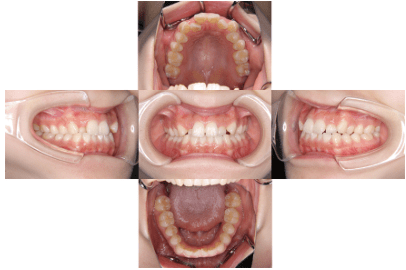

治療後

• 初診時年齢:16歳

• 主訴:叢生

• 診断:叢生を伴う骨格性I級症例、非抜歯

• 治療内容:顎が狭く、上の前歯が後ろに生えてしまい、ガタガタして上手く咬めない状態でした。幅を広くして、歯の角度を調整し、自然な位置に並べたので上手く咬めるようになりました。

• 治療期間:2年

• リスク:ブラックトライアングル(歯と歯の間と歯ぐきの間の三角形の隙間)が強くでる場合がある

• 費用:90万円